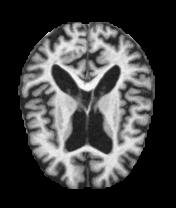

Moderate Dementia

Severe tissue loss

Real MRI scans showing progressive structural brain changes across all dementia stages

- • Total Images: 6,400+ brain scans

- • Normal Cognition: 3,200 cases

- • Very Mild Dementia: 2,240 cases

- • Mild Dementia: 896 cases

- • Moderate Dementia: 64 cases